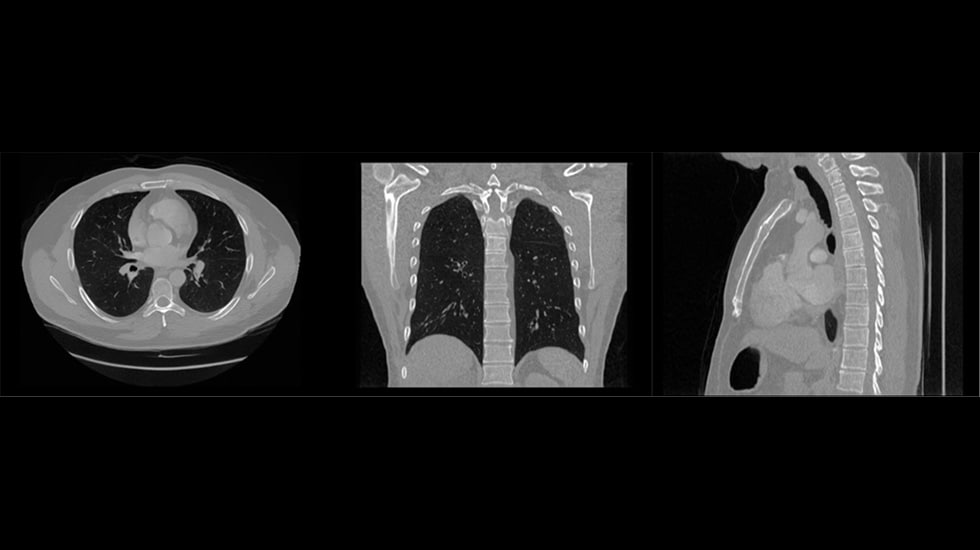

Overcoming these limitations requires thinking beyond traditional data sources. At Philips, we are exploring this challenge with a promising approach: realistic, algorithmically generated Computed Tomography (CT) and Magnetic Resonance Imaging (MRI) scans. Large-scale synthetic medical image datasets enable AI models to learn from a diverse and extensive range of population samples, improving their accuracy and robustness, while their algorithmic generation helps protect sensitive patient data and dispel privacy concerns.

Disclaimer: These images were produced as part of exploratory research into synthetic medical imaging and do not represent finalized outputs or validated clinical use cases.

Our work with synthetic CT data targeting tumor detection and classification shows encouraging preliminary results. The insights we gain from this project will serve as a launchpad for expanding into cardiovascular applications and, ultimately, a multi-modality engine that can strengthen AI across a wide range of diagnostic use cases.